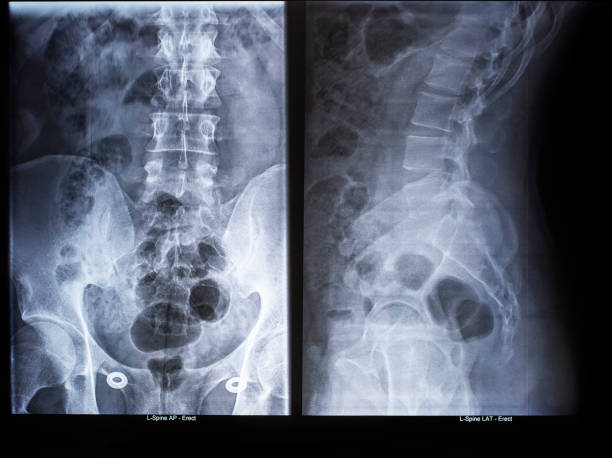

Delve into the intricate world of orthopedic tumors with Dr. Mishil Parikh, a distinguished Tumor Ortho Surgeon in Mumbai. This article offers an in-depth exploration of the causes, symptoms, and risk factors associated with bone tumors, underlining the significance of early detection.

Learn about cutting-edge diagnostic tools and treatment options available at Dr. Parikh's clinic. Gain insights into the preventive measures to thwart the onset of orthopedic tumors.